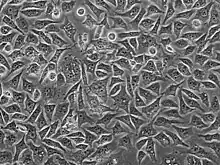

PC3 (PC-3) is a human prostate cancer cell line used in prostate cancer research and drug development.[1] PC3 cells are useful in investigating biochemical changes in advanced prostate cancer cells and in assessing their response to chemotherapeutic agents. PC3 cells are also used to study viral infection in mammalian cells that exhibit an immune response.[2]

The PC3 cell line was established in 1979 from bone metastasis of grade IV of prostate cancer in a 62-year-old Caucasian male.[3] These cells do not respond to androgens, glucocorticoids or fibroblast growth factors,[4] but results suggest that the cells are influenced by epidermal growth factors.[5] PC3 cells can be used to create subcutaneous tumor xenografts in mice to investigate the tumor environment and therapeutic drug functionality.[6]

PC3 cells have low testosterone-5-alpha reductase and acidic phosphatase activity, and do not express PSA (prostate-specific antigen). Furthermore, karyotypic analysis has shown that PC3 are near-triploid, having 62 chromosomes. Q-band analysis showed no Y chromosome. From a morphological point of view, electron microscopy revealed that PC3 cells show characteristics of a poorly-differentiated adenocarcinoma. They have features common to neoplastic cells of epithelial origins, such as numerous microvilli, junctional complexes, abnormal nuclei and nucleoli, abnormal mitochondria, annulate lamellae, and lipoidal bodies.